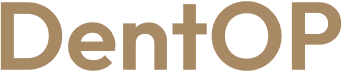

Lucrările și implanturile dentare vechi l-au determinat să refacă intervenția cu dantură fixă

Procedurile de inserare a implanturilor dentare determină schimbări o dată cu trecerea timpului. În cazul domnului A. lucrările vechi și implanturile inserate nu-i mai asigurau o bună masticație. Este important să ne prezentăm la medicul stomatolog și să verificăm lucrările efectuate cu mult timp în urmă, deoarece ele pot să dezvolte afecțiuni severe.

După o analiză amănunțită a problemelor dentare și a stării generale de sănătate, Dr Cazacu Corrado, a decis un plan de tratament cu implanturi dentare. Pacientul nostru, fiind bine informat a confirmat planul propus de către Medicul Specialist Chirurgie Dento-Alveolară și astfel, dantura lui este acum una sănătoasă.

S-au inserat lucrări provizorii imediat după intervenție, iar pacientul le-a purtat timp de 6 luni, timp în care a avut grijă ca alimentația sa să fie una moale, protejând astfel vindecarea implanturilor.

A fost un proces de durată, dar pacientul nu a stat fără dantură și a urmat în totalitate indicațiile medicale. A ajuns astfel ca după șase luni să aibă un zâmbet nou, sănătos și cu ajutorul căruia își poate relua liniștit și viața socială.